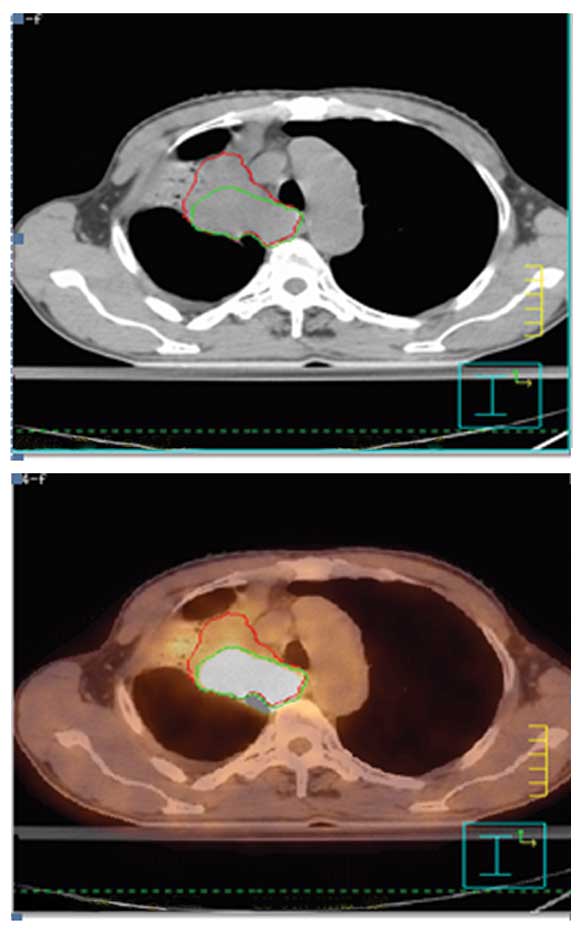

What Cancers Are Detected By Pet Scan : Lung Cancer, Ct And Pet Scans Photograph by Du Cane ... - With that being said, not all cancers can be detected by pet.. Those are detected by pet scanner and a computer converts a signal into detailed images showing how organs are working. Pet scans, short for positron emission tomography, can detect areas of cancer by obtaining images of the body's cells as they work. A pet scan shows how your tissues and organs are functioning. A pet scan may not be possible if you are obese and unable to fit into the scanning chamber (gantry). It also can let you and your doctors know if cancer treatment is working.

With that being said, not all cancers can be detected by pet. Pet can detect extremely small cancerous tumors, subtle changes of the brain and heart, and give doctors important early although cancer spreads silently in the body, pet can inspect all organs of the body for cancer in a single examination. Pet scans, short for positron emission tomography, can detect areas of cancer by obtaining images of the body's cells as they work. Pet scanners work by detecting the radiation given off by a substance injected into your arm called a radiotracer as it collects in different parts of your body. It can also pick up advanced cancers that standard tests like computerized tomography (ct) and bone scans often miss.

Ultrasound is also used to image the abdominal organs and kidneys. In this case, your body position will be very important. Pet scans are very useful in detecting diseases like cancer because tumors will be a different color than surrounding tissue activity. Positron emission tomography (pet) imaging or pet scan is a nuclear medicine imaging. A pet scan can help detect which parts of the heart have been damaged or scarred, and it can help identify circulation problems in the. Today, most pet scans are performed on instruments. Those are detected by pet scanner and a computer converts a signal into detailed images showing how organs are working. Diagnosis, cancer staging, treatment diagnosed with cancer and are undergoing active treatment, assess treatment response efficiency and perform cancer monitoring with pet/ct scan! Pet is speeding the detection of new drug weapons in the war on cancer. A pet scan is most often used when other tests, such as mri scan or ct scan, do not provide enough information or physicians are looking for the potential spread of the breast cancer to lymph nodes or beyond. Pet scans are most commonly used to detect: Most pet scans use a type of radiolabeled sugar to detect the cancer, as the majority of cancers grow quickly and need sugar for that growth. Pet scans, short for positron emission tomography, can detect areas of cancer by obtaining images of the body's cells as they work.

Pet/ct, which is a combination of positron emission tomography (pet) with computerized tomography (ct), is a powerful, essential tool for cancer detection and diagnosis. Pet/ct method has no competitors in oncology that could equally detect: Pet scans are particularly helpful for investigating confirmed cases of cancer to determine how far the cancer has spread and how well it's. Ultrasound is also used to image the abdominal organs and kidneys. Prostate cancer that spreads or comes back after treatment is often small and hard to detect.

Pet scans also prevent unnecessary surgeries and help suggest which cancer therapies are likely to be most effective for specific tumor types. Cancer patients and their doctors now have access to a superior imaging technology in pet scans. Pet scans use radioactively tagged molecules (or tracers) to image a wide array of molecular processes and when detected by a pet scanner, the tracers help your doctor to see how well your organs and tissues are working. For cancer and disease detection, the most commonly used nuclear scan is an fdg pet scan. Pet scans can reveal the presence and stage of a cancer, show whether and where it has spread, and help doctors decide on treatment. The pet scan uses a mildly radioactive drug to show up areas of your body where cells are more active than normal. Pet/ct method has no competitors in oncology that could equally detect: Pet/ct scans provide significantly more information than ct scans, and are far more reliable when diagnosing cancer. A pet scan may not be possible if you are obese and unable to fit into the scanning chamber (gantry). Because of this high level of chemical activity, cancer cells the combined use of pet scans and ct scans is an effective method for detecting pelvic recurrences of rectal cancer. The tracer will collect in areas of. Prostate cancer that spreads or comes back after treatment is often small and hard to detect. A pet scan, which uses a small amount of radioactive material, can help show if an enlarged lymph node is cancerous and detect cancer cells throughout the body that may not be seen on a ct scan.